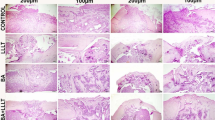

With regard to microscopic parameters (Fig. 3), better results were found for group A than for group B (Fig. 4a, b). The fracture sites from all rats sacrificed at day 8 (subgroups A1 and B1) showed similar degrees of inflammatory infiltration, whereas only the rats of subgroup A2 (on day 13) showed a significantly lowered inflammatory infiltration response (p = 0.015), as shown in Fig. 5a, b. This lower degree of inflammation was maintained at day 18 (subgroup A3; p = 0.028). LLLT rats in subgroups A1, A2, and A3 showed an emergence of trabecular bone formation over time, with significant differences among the three subgroups measured (p < 0.01 for all 3 days). In contrast, no trabecular matrix formation was observed for any of the control rats (subgroups B1, B2, or B3). Periosteal formation was not seen in any of the rats after 8 days of healing (subgroup A1 and B1), but a high percentage of animals with periosteal formation were found by day 13 in the LLLT group (subgroup A2) as compared with control rats at the same time point (subgroup B2; p = 0.001). This increased periosteal response at day 13 was maintained to day 18 for LLLT rats (subgroup A3) whereas control rats at day 18 had only just started to show periosteal differences (subgroup B3 p = 0.005). With regard to bone formation, significant differences were measured among the groups at each time point, with better results identified for LLLT rats (subgroups A1, A2, and A3) as compared with their respective control counterparts (subgroups B1, B2, and B3; p < 0.001 for all periods).

Morphometric analysis. Similar inflammatory infiltration was observed for LLLT and control rats at day 8 (subgroups A1 and B1). A significant reduction in inflammatory infiltration was only observed for LLLT rats at day 13 (subgroup A2). Trabecular matrix formation was found in all of the LLLT rats (group A). Periosteal formation was not seen at day 8 in either group (subgroups A1 and B1) but was present in the LLLT rats at days 13 and 18 (subgroups A2 and A3). A significant difference in new bone formation was observed for LLLT rats at all time points (p < 0.001)

Histological sections after 13 days. a LLLT rats; it is possible to observe trabecular bone matrix formation (cross), inflammatory infiltration (arrow), chondrocytes presence (triangle), and periosteum formation (sphere). b Control rats; fibroblast re-composition (star) and inflammatory infiltration (thick arrow) can be observed

Immunohistochemistry results (Fig. 6) showed higher expression of osteocalcin in the tissue samples from LLLT rats (subgroup A1) at day 8 as compared with that from the control rats at the same time point (subgroup B1; p = 0.007). Whereas expression of osteocalcin increased for the control rats by day 13 (subgroup B2), osteocalcin expression remained higher for LLLT rats (subgroup A2). These results indicate that LLLT rats (group A) had an anticipation on bone-remodeling response as compared with control rats (group B). By day 18, rats in both groups showed no changes in osteocalcin expression from day 13. Osteopontin showed the expected behavior (increase on days 8 and 18 and decrease on day 13) in both groups. The difference between the LLLT and the control group was significant only on day 8 (p = 0.033). LLLT and control rats showed similar expression changes for osteonectin. Control rats at day 13 (subgroup B2) showed a lower expression of osteonectin as compared with the LLLT rats at that same time point (p = 0.018), and no significant difference was observed for osteonectin expression by day 18 between the two groups.

Immunohistochemical analysis. Osteocalcin and osteopontin were detected early in LLLT rats (group A) with statistical significance observed at day 8 (subgroup A1) as compared with the control rats at that same time point. Osteonectin expression was significantly higher in LLLT rats at day 13 (subgroup A2), as was periosteum formation. None of the proteins showed any difference in expression at day 18 between the two groups (groups A and B)

The reduction in inflammatory infiltration observed in at days 13 and 18 in the LLLT rats led us to assume that these rats were possibly less affected by the inflammatory phase of bone repair, thus allowing for an earlier reparative phase and, consequently, earlier new bone formation, as previously observed [29]. Inflammatory infiltration is part of the bone remodeling process, and it is useful if not drawn out, as longer inflammatory periods compromise the final bone quality. Laser irradiation did not eliminate the inflammation; rather, it expedited all of the steps involved in bone formation, including this inflammatory phase. The reduction in inflammatory infiltration, together with the increase in periosteal development and considerable increase in trabecular matrix formation, showed that rats in the LLLT group underwent an earlier and more organized process of bone formation. In the absence of LLLT, however, no significant trabecular matrix was formed, which is indicative of a slower and less-organized process.

At the cut edge of the fracture, both osteocalcin and osteopontin—two proteins associated with extracellular matrix formation and osteoblast activity [30]—were detected early in LLLT rats, which is consonant with the microscopic results. This is very important, as these matrix factors contribute to the growth, shape, and size of the bone matrix, and affect the quality of the matrix that is produced [31]. Indeed, LLLT and its potent effect on increasing proliferation and cell viability may significantly contribute to many biomedical resources that augment tissue formation and repair in regenerative medicine [32]. Thurner’s study [31] on osteopontin deficiency showed a 30 % decrease in fracture toughness in the absence of the protein, suggesting an important role for osteopontin in impeding crack propagation. Its presence on the surface of samples in “in vivo” bone experiments also suggests its involvement in the process of cell-matrix adhesion, and matrix-matrix modeling and remodeling [33]. Our results also suggest a possible connection between the emergence of osteonectin and the formation of the periosteum, both of which are involved in callus formation. A significant amount of osteonectin during this stage adds to the progress of bone formation, because it incorporates collagen, an important protein required for the acquisition of the tensile strength of the bone. The mineralization and subsequent completion of the repair process of a fracture can be achieved only when proteins that have an affinity for calcium (such as osteocalcin and osteopontin) promote mineral deposition, and those with an affinity for collagen (such as osteonectin) promote bone strength.